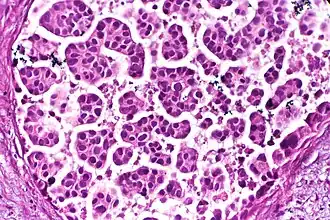

Nests: islands of cells of similar type. -

Solid: More or less the same cell type throughout, with no spaces between, and no other particular pattern. -